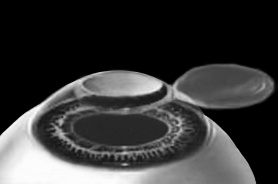

Итак, головка присоединяется к вакуумному кольцу и по специальным полозьям двигается над куполом роговицы (рис. 3). Срез, или отслаивание (называйте, как хотите), проводится не полностью, у крышечки (роговичного лоскута) остается маленький участок на периферии, соединяющий ее с роговицей (рис. 4).

Рис. 4. Роговичный лоскут сформирован.

Иллюстрация с сайта Международного лазерного центра www.optics.ru